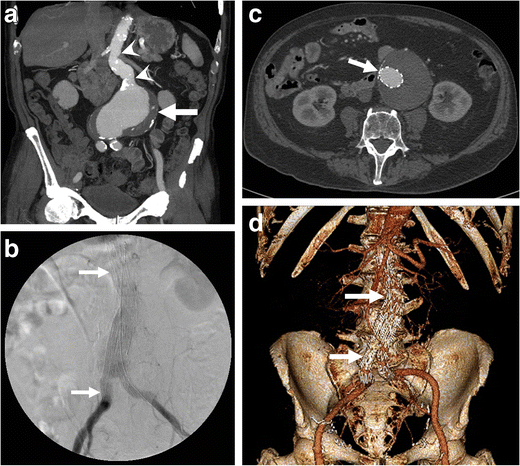

Aortocaval fistula

Aortocaval fistula. a Axial arterial phase enhanced CT shows simultaneous enhancement of the AAA and IVC in an 83-year-old man with AAA rupture and retroperitoneal haematoma (R). b Axial enhanced CT of the same patient at a lower level demonstrates active contrast extravasation (white arrows) from the aortic aneurysm to the IVC with loss of normal fat planes between the structures. Retroperitoneal haematoma (R) can also be seen

Endovascular aneurysm repair. a Coronal enhanced CT image of an 85-year-old man presenting with an impending AAA rupture (same as Fig. 5) demonstrates a large AAA (white arrow) with a long proximal neck (white arrowheads). b Fluoroscopy image, c axial, and d 3D rendering of the same patient show a deployed aorto-biiliac stent-graft (white arrows)